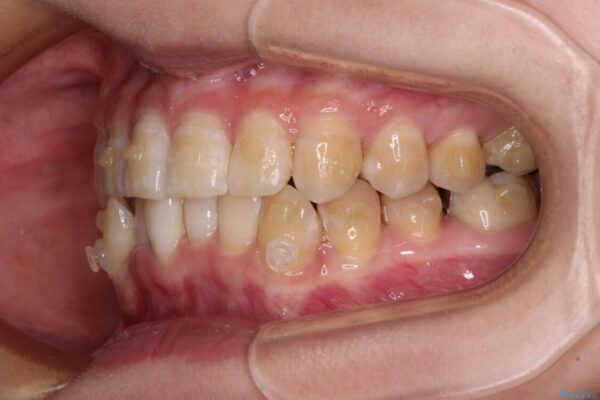

下顎の八重歯を気にして来院された患者様です。

下顎前歯にデコボコが集中していたため、顎間ゴムによる後方移動とIPR(歯と歯の間を削ること)により歯列を整えることとしました。

治療前、下顎前歯のデコボコが集中しており、奥歯の咬み合わせは、上顎に対して下顎が前方位にある状態でした。下顎の歯列を後方へ移動させる治療はインビザラインの得意とするところですので、1年程度で無事に治療を終えることができました。

治療途中

• 【モニター】下顎前歯のデコボコをインビザラインできれいに 治療途中画像